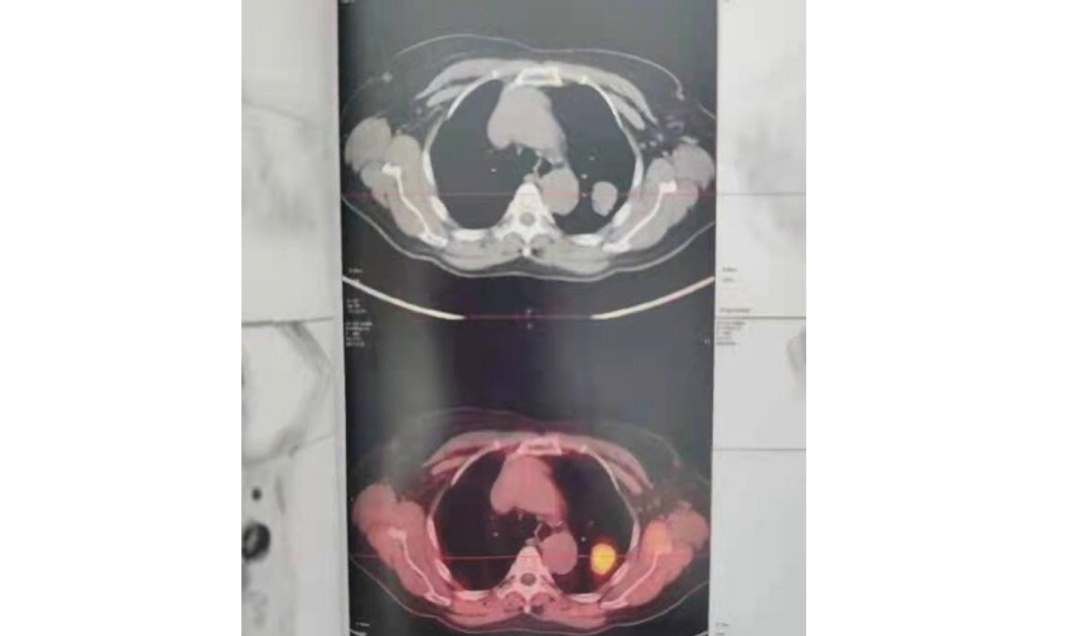

平扫CT肺窗

平扫CT纵隔窗密度约40HU

增强CT纵隔窗,肺结节密度增高至60HU,考虑恶性肿瘤

PET-CT显示病灶糖代谢摄取高,

诊断为恶性肿瘤